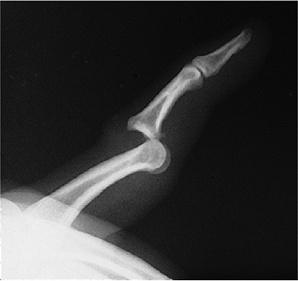

When dislocations do occur they are most

diminished skin coverage over this joint (Figure 10-1A). -

Reduction is achieved by longitudinal traction and manipulation of the base of the phalanx into its anatomical bed.

As in all reductions, joint stability is evaluated by gentle passive and active motion.

Postreduction radiographs are taken to verify the reduction.

The joint is splinted in a few degrees of flexion, and motion may be started in 7 to 10 days (Figure 10-1B).

Figure 10-1 (A) X-ray appearance of a dorsal dislocation of the IP joint of the thumb. (B) X-ray appearance after reduction and splinting.